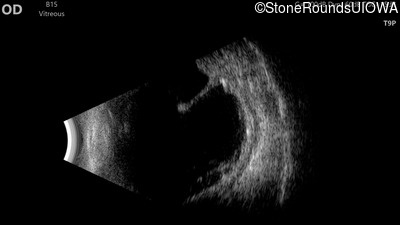

Visit at age: 13 years (Visit 2)

B-Scan Ultrasonography - Right - 20/500

Exemplar